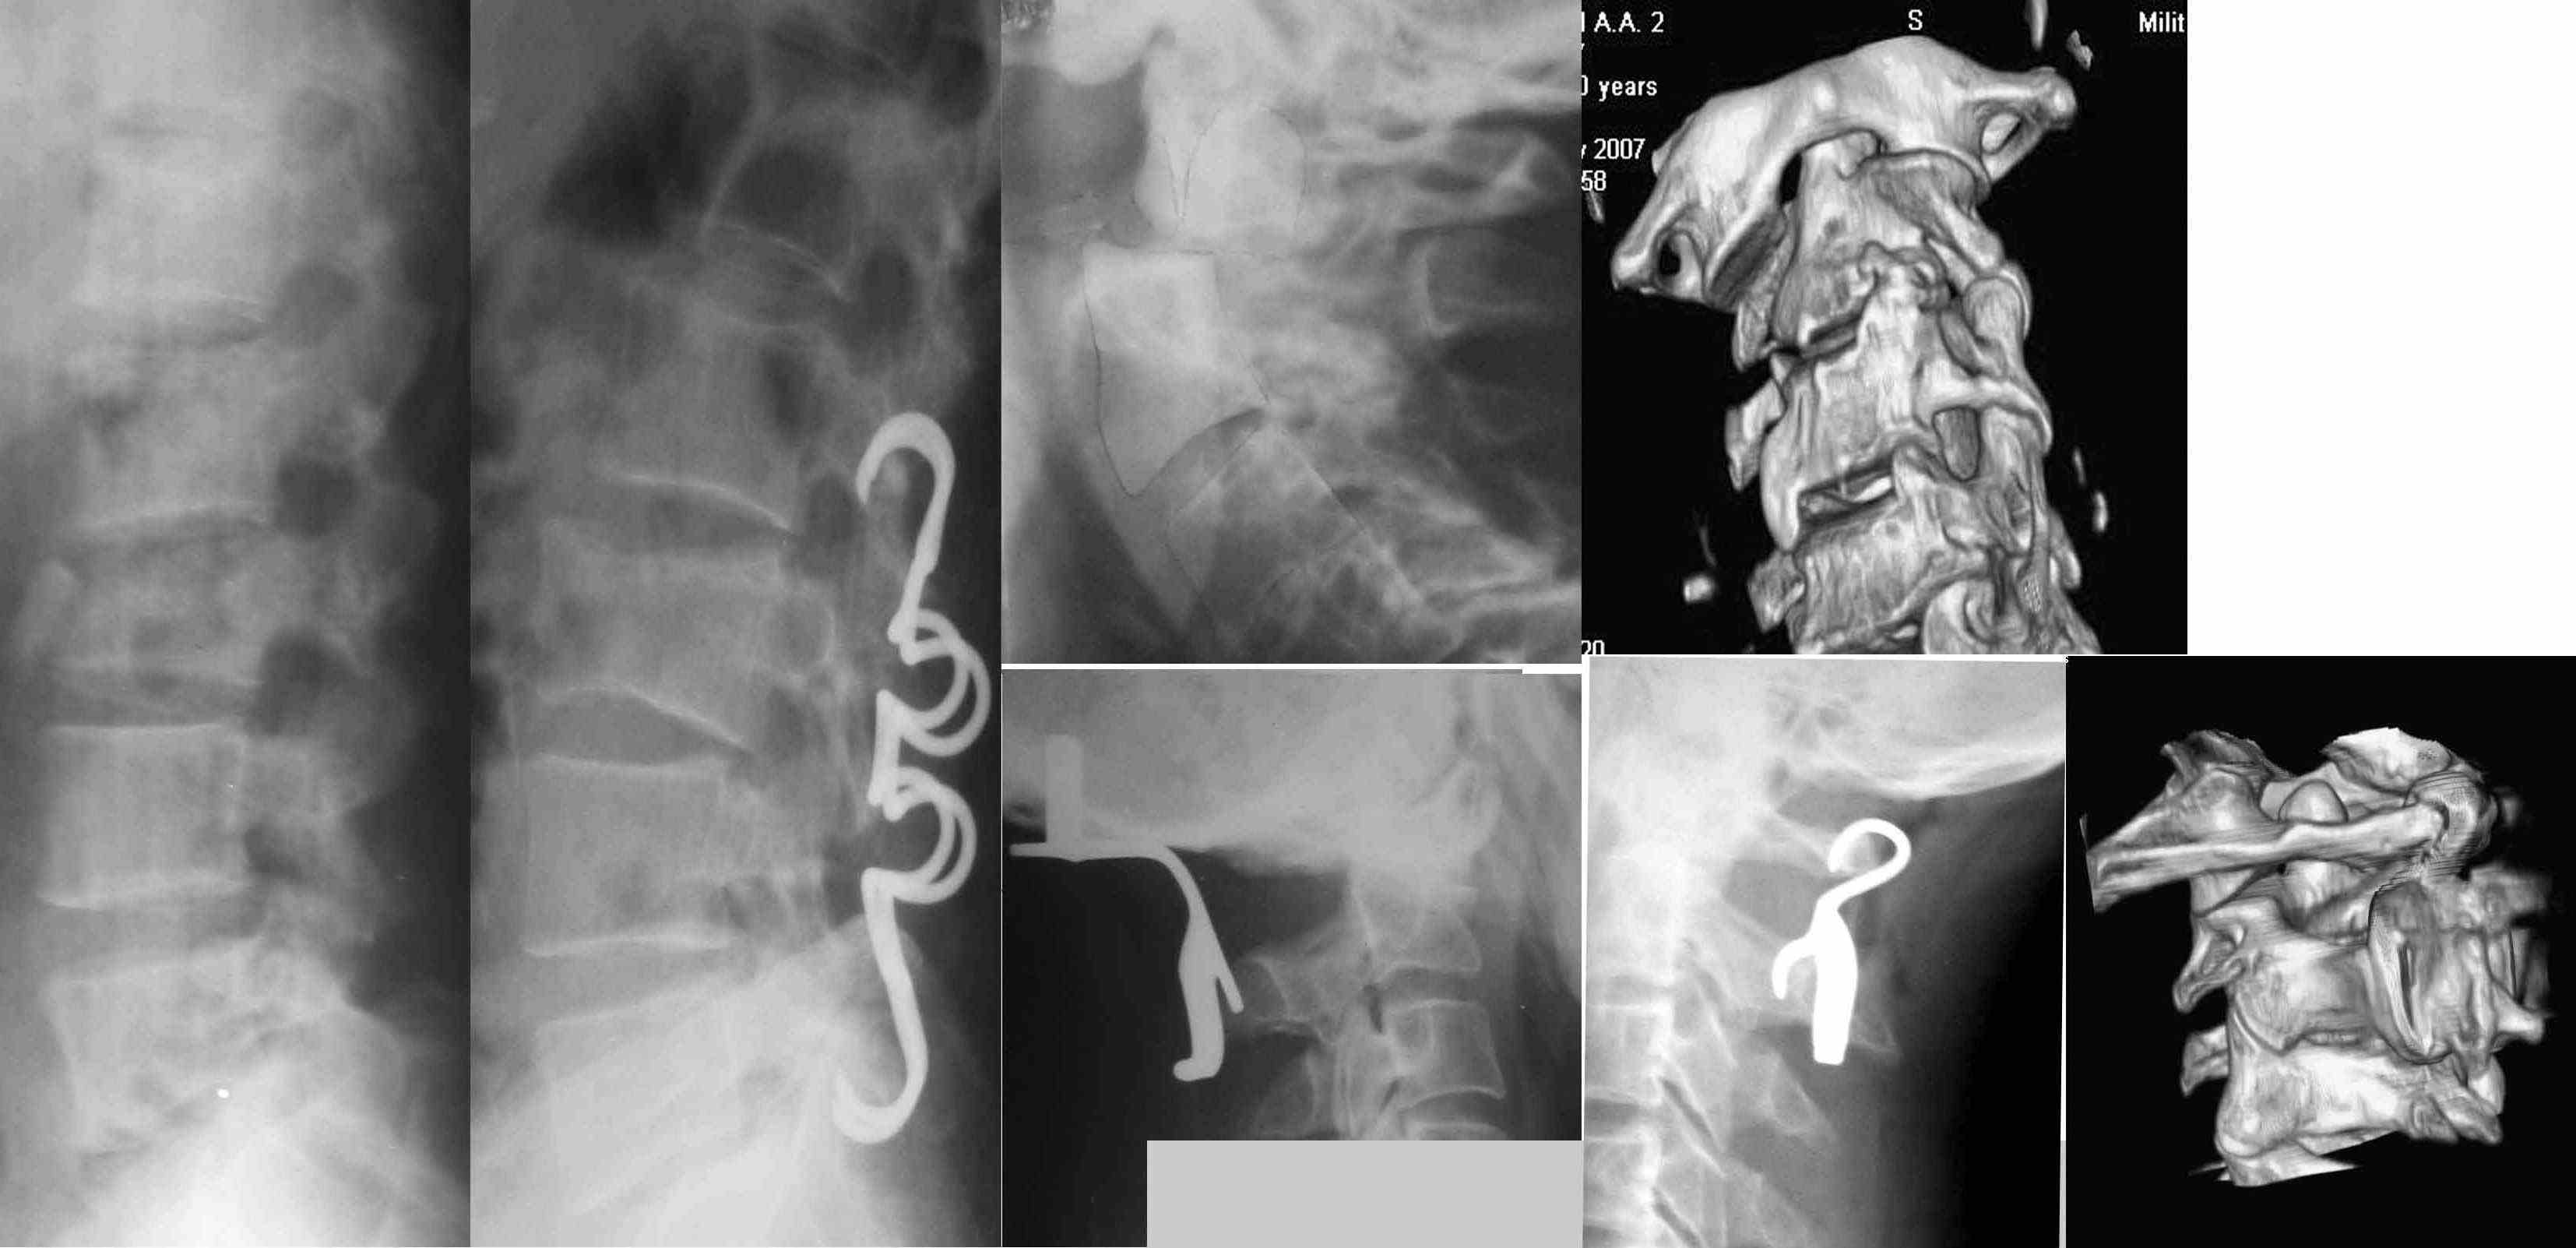

Достаточно удобны скобы для задней динамической фиксации позвоночника.

Действительно уникальные конструкции, не имеющие аналогов - это скобы для окципитоспондилодеза и атланто-аксиального спондилодеза.